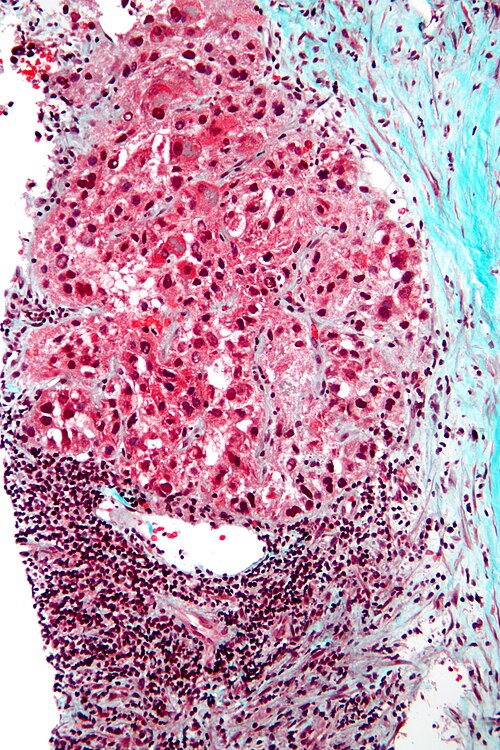

El diagnóstico definitivo del carcinoma hepatocelular suele requerir la obtención de tejido mediante biopsia hepática, la cual permite la confirmación histopatológica del tumor. Sin embargo, esta técnica invasiva conlleva ciertos riesgos, entre los que destaca la posibilidad de diseminación tumoral a lo largo del trayecto de la aguja, fenómeno conocido como siembra, que ocurre en aproximadamente uno a tres por ciento de los casos. Debido a esta complicación potencial, la indicación de la biopsia debe evaluarse cuidadosamente, considerando tanto las características del tumor como la situación clínica del paciente.